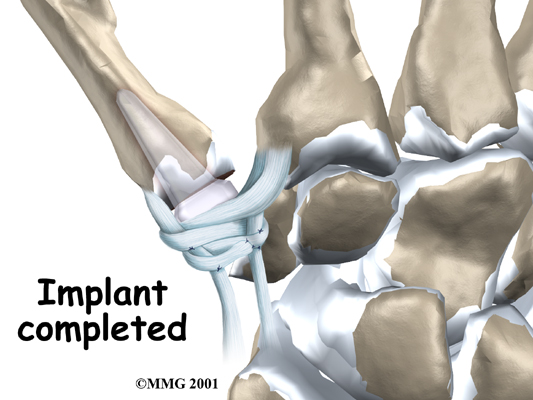

A burr (a small cutting tool) is used to make a canal into the bones that form the thumb joint. The surgeon sizes the stem of the prosthesis to ensure a snug fit into the canal and inserts it. When the new joint is in place, the surgeon wraps the joint with a strip of nearby tendon. This gives the new implant some added protection and stability.

The skin is stitched together and a splint applied.

The soft tissues are sewn together, and the thumb is splinted and bandaged.

View animation of tendon strip addition